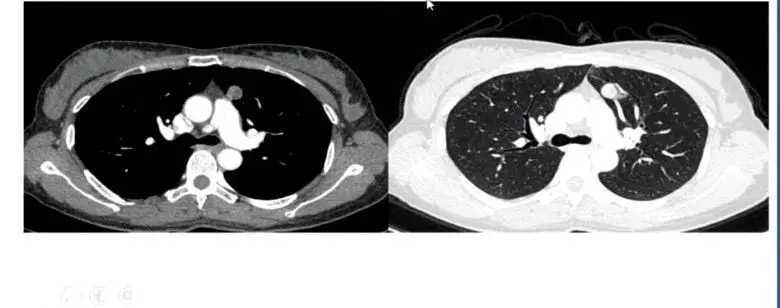

隐球菌感染范围扩大形成实变后,治疗前后影像表现会有明显变化。

图14 隐球菌实变治疗前后对比